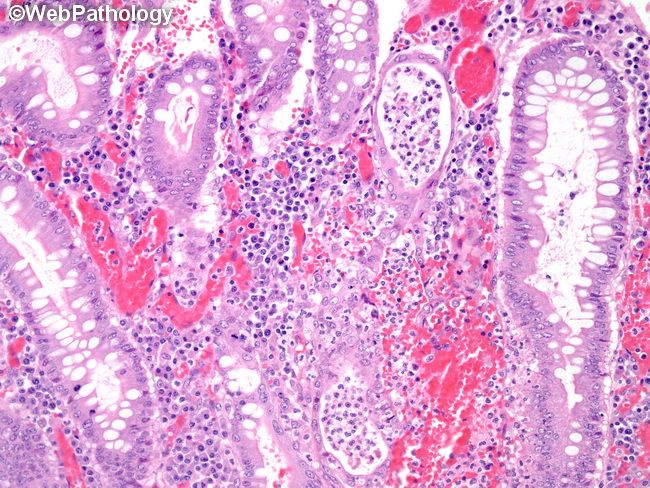

Патанатомия рниму пф 118 фото